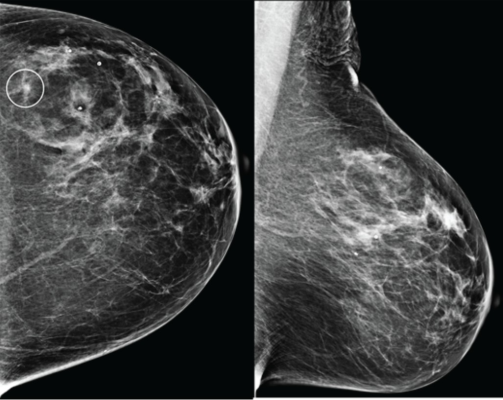

Craniocaudal (left) and mediolateral oblique (right) digital mammography images of left breast were assessed by interpreting radiologist as BI-RADS category 1, consistent with negative result. Artificial intelligence (AI) system flagged asymmetry in lateral breast on CC view (circle) and categorized examination as intermediate risk, consistent with negative or positive result depending on threshold used for categorizing AI results. Patient was not diagnosed with breast cancer within 1 year after screening examination, consistent with negative outcome according to present study’s reference standard. Thus, interpretation by radiologist was true negative and by AI system was positive if defining both intermediate-risk and elevated-risk categories as positive. Annotation was not generated by AI system but rather was recreated by present authors based on AI output coordinates.